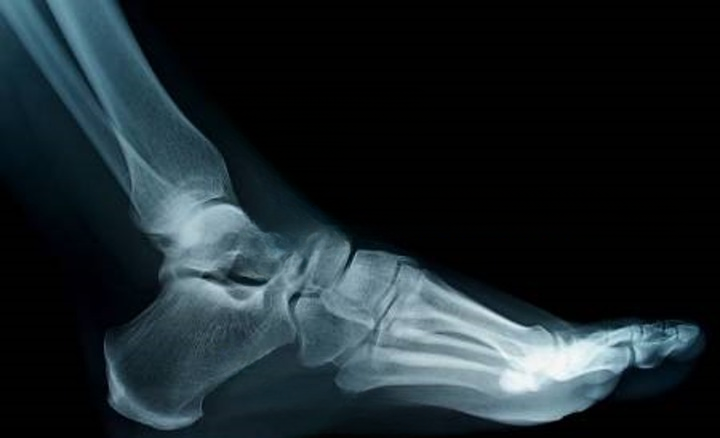

HyProCure is procedure which inserting a small, titanium stent to align the bones of the heel and ankle. Schedule an appointment now at Feldman & Leavitt Foot and Ankle Specialists, your Top Rated Podiatrist for HyProCure in Cranston, Calgary, Alberta

HyProCure corrects irregular foot form and alignment. The procedure uses an incision in your arch to correct the misaligned bones in your foot, allowing your bones to move freely again. HyProCure also reduces pressure on nerves, which can cause pain and inflammation.

HyProCure is place in the naturally occurring space between your bones to instantly realign and stabilize the hindfoot. It will not penetrate or be implanted into your bones.